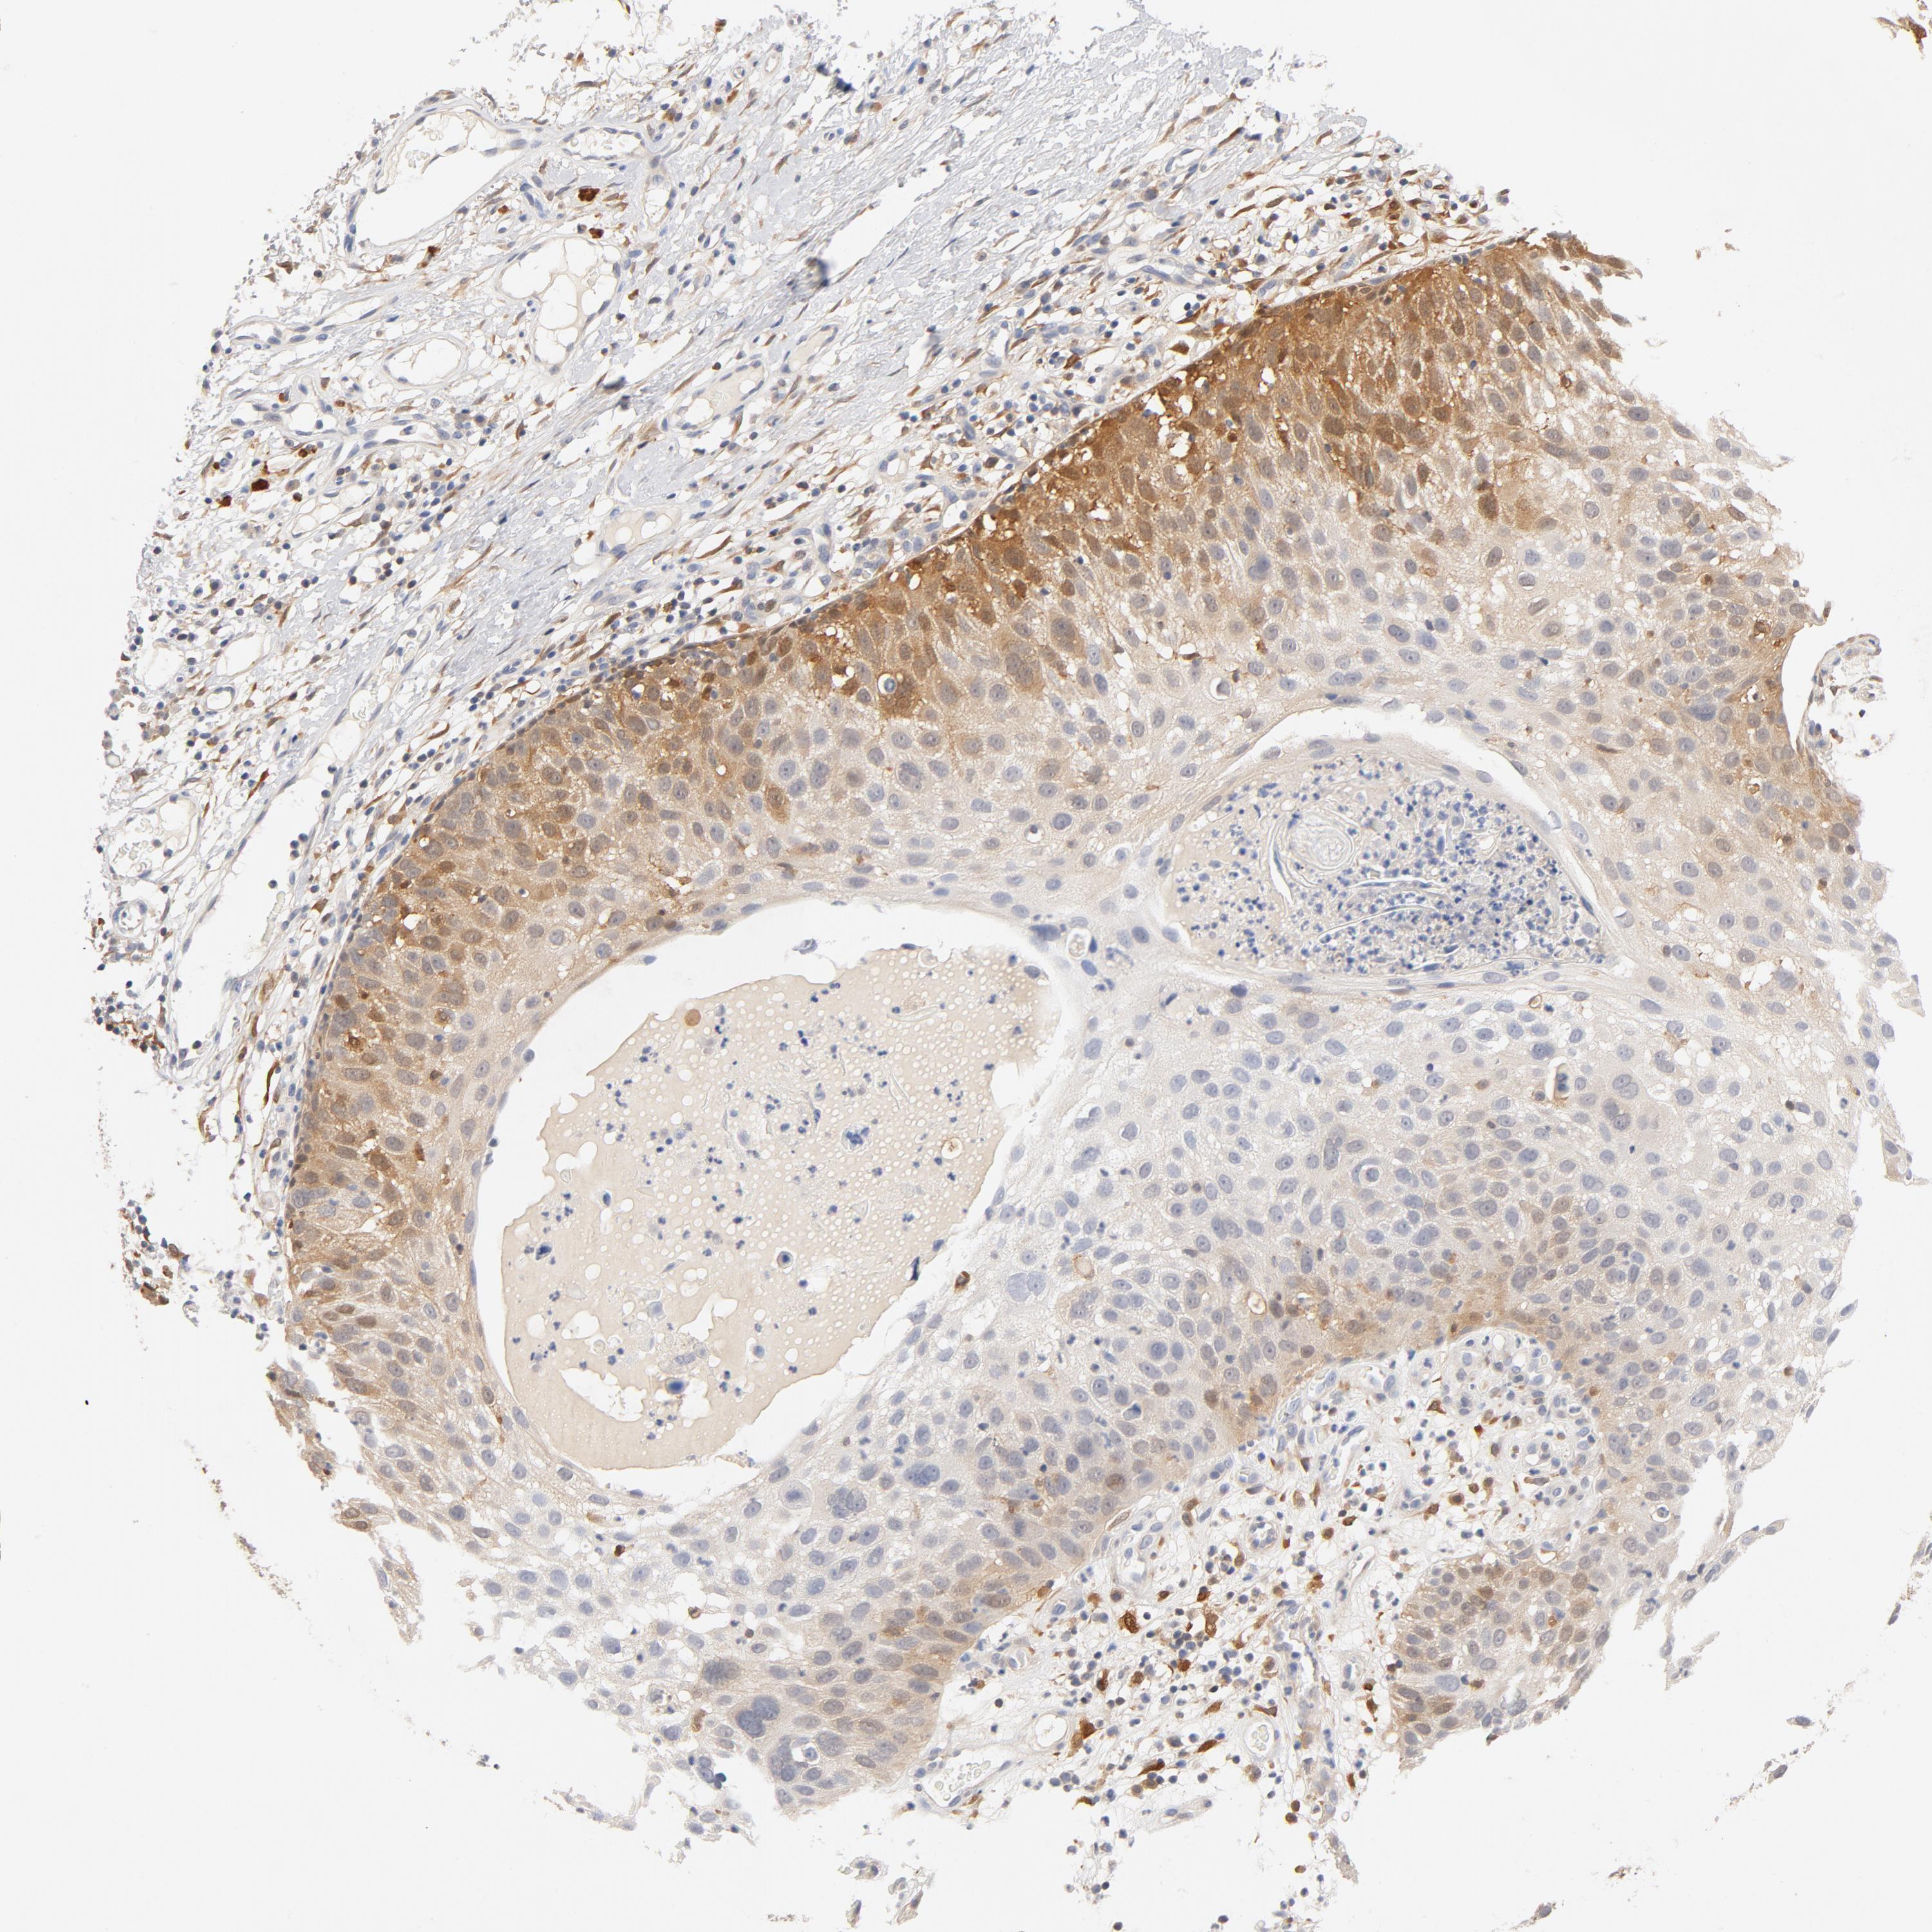

CANCER SKIN CANCER Show tissue menu

Basal cell and squamous cell cancer

SKIN CANCER - Protein expressioni

A mouse-over function shows sample information and annotation data. Click on an image to view it in a full screen mode. Samples can be filtered based on level of antibody staining by selecting one or several of the following categories: high, medium, low and not detected. The assay and annotation is described here.

Each image is clickable and will lead to virtual microscopy that enables deeper exploration of all samples and also displays staining intensity scores, fraction scores and subcellular localization as well as patient and tissue information for each sample.

Antibody HPA000931

Antibody HPA000982

Antibody CAB004049

Staining

High

Medium

Low

Not detected

Intensity

Strong

Moderate

Weak

Negative

Quantity

>75%

75%-25%

<25%

None

Location

Nuclear

Cytoplasmic/membranous

Cytoplasmic/membranous,nuclear

Squamous cell carcinoma, NOS

Basal cell carcinoma